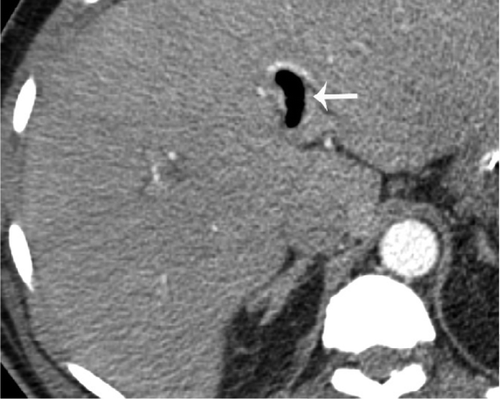

В частности, как пояснил специалист, у некоторых пациентов с COVID-19 внезапно развивался пневматоз - патологическое состояние системы пищеварения, при котором газы проникают в толщу стенки кишечника и образуют там воздушные кисты. Кроме того, у нескольких людей было выявлено необычное желтое обесцвечивание кишечника, еще у трех больных - инфаркт кишечника.

© Radiology